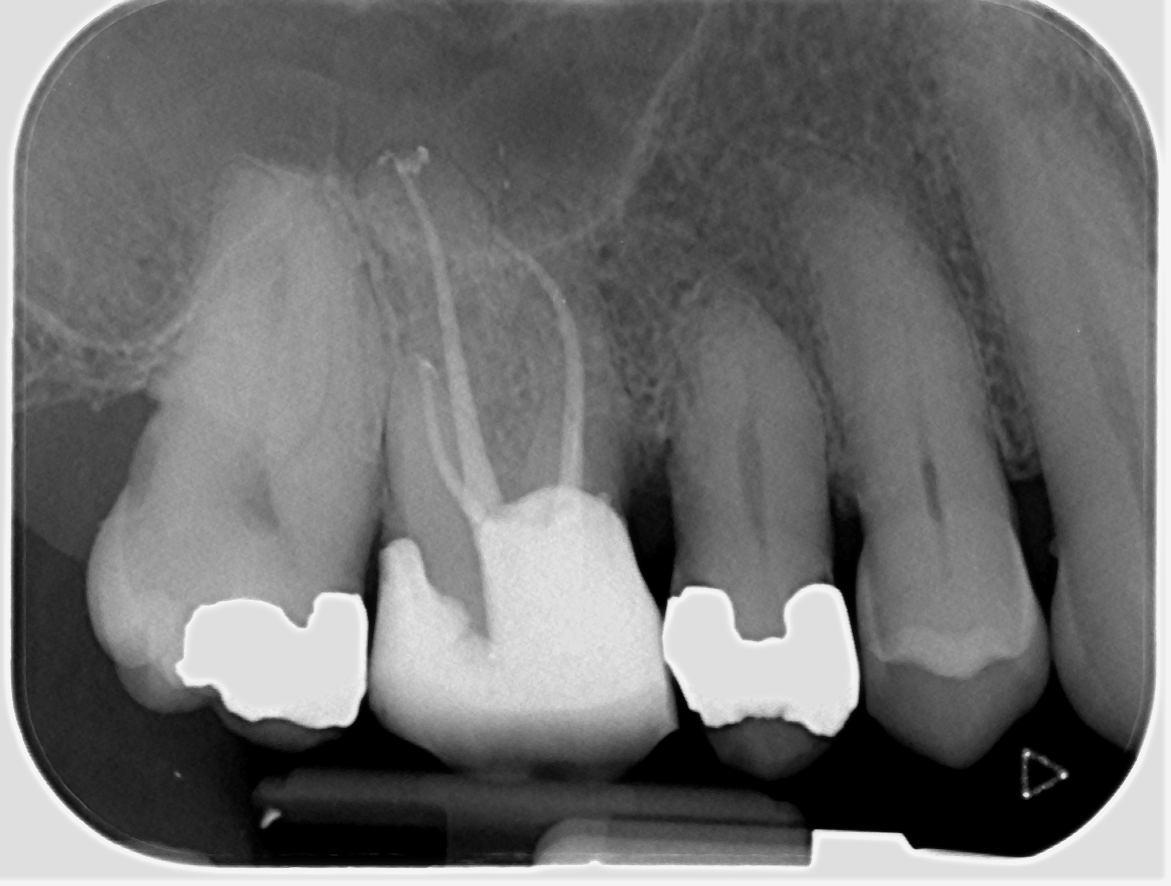

2-visit reRCT UR6 - insane apical delta anatomy P and MB canals - all thanks to the power of hypochlorite!🤣 Edge Endo preps VC obturation #savingteeth #endodontics

2-visit reRCT UR6 - insane apical delta anatomy P and MB canals - all thanks to the power of hypochlorite!🤣

Edge Endo preps VC obturation #savingteeth #endodontics